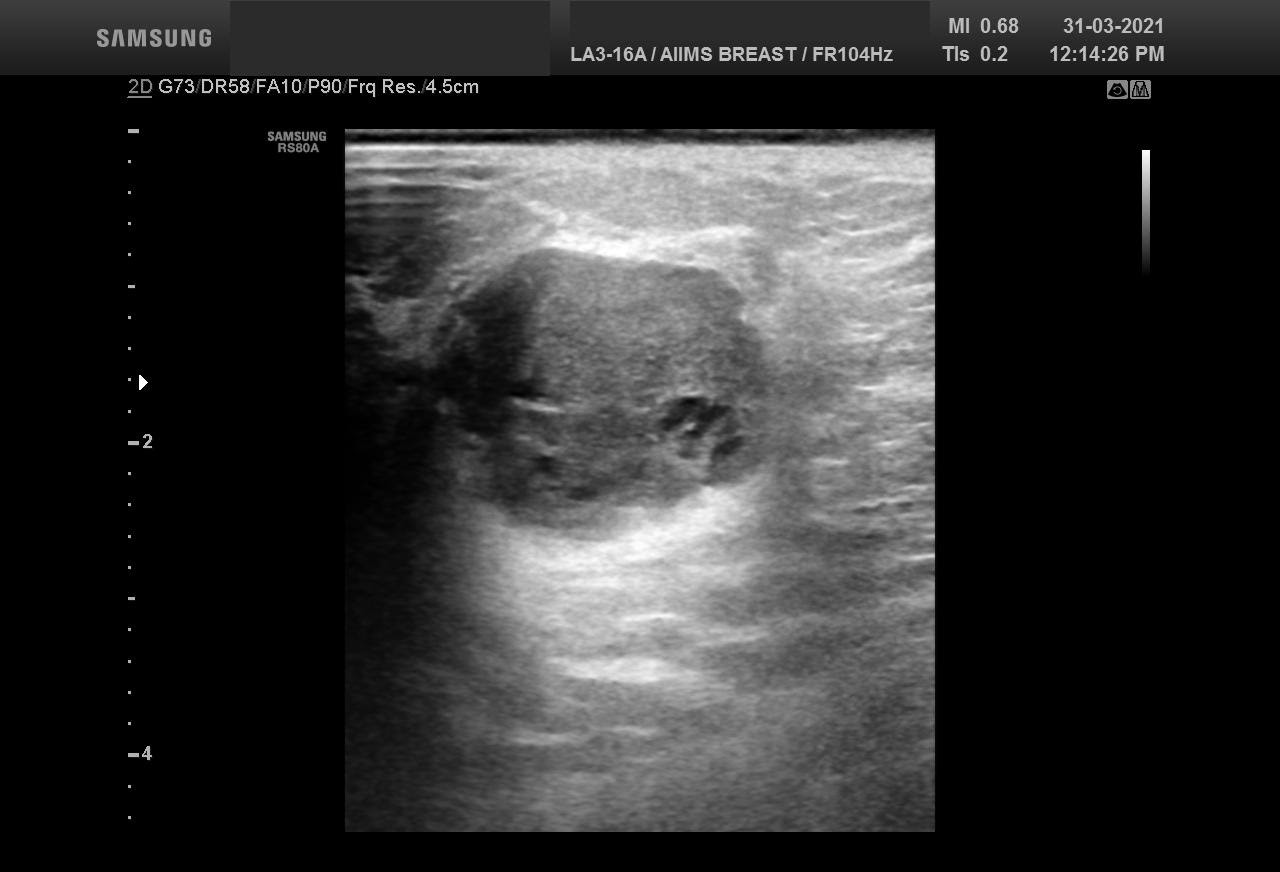

Bilateral Digital mammography , Craniocaudal (CC) and Mediolateral oblique (MLO) view with tomosynthesis images revealed a round shaped, equal density mass with indistinct margin in lower outer quadrant. No suspicious microcalcifications was seen. No significant axillary lymph nodes were present. A high resolution ultrasound of the right breast showed a round shaped, heterogeneously hypoechoic mass with irregular margin, small cystic spaces within and posterior acoustic enhancement, measuring about 1.6x1.9x1.5cm at 7 O’clock position. Mild internal vascularity was noted on colour doppler images. Right axilla showed suspicious lymph nodes with loss of fatty hilum and thickened cortex.

Although the mass has few benign features like round shape and posterior enhancement, presence of irregular margin and axillary nodes with thickened cortex and loss of fatty hilum points towards the suspicious nature of the mass. So, the mass was classified as BIRADS category 4b lesion. Ultrasound guided biopsy of the mass was suggestive of invasive breast carcinoma with possibility of medullary carcinoma. IHC study showed tumor to be Positive for PR and negative for ER and HER2neu receptors. Patient underwent Breast conserving surgery with right axillary lymph node dissection and final histopathological report was Invasive carcinoma with medullary features. Axillary lymph nodes were involved by the tumor.